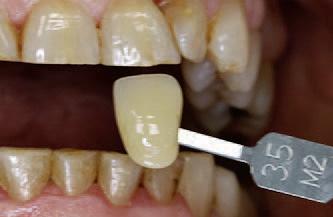

Tooth Shade Determination & Workflow

With VITA EasyShade V

Standardising visual tooth shade determination and precise shade reproduction are some of the everyday challenges faced in dental practices. The perception of colour is based on subjective, visual sensory impressions and is influenced by a number of factors. For example, lighting conditions have a significant impact on the shade chosen during tooth shade determination. The basic shade of the tooth is mainly defined by the dentine, while the layers of enamel on top produce a variety of optical effects, depending on the thickness and translucency. In the following case, dentist Dr. José Gabriel Martínez demonstrates how easy and reliable tooth shade determination and material selection can be using the VITA Easyshade V digital spectrophotometer (VITA Zahnfabrik, Bad Säckingen, Germany).

independently from the ambient conditions and the tooth shade was determined. This procedure was used to determine the 2M2 tooth shade for the patient and to select the systemrecommended VITABLOCS RealLife blank (VITA Zahnfabrik, Bad Säckingen, Germany). In order to provide the dental technician with detailed information on the results, additional digital photos were created in RAW format. The photographs were taken using the shade guide and a polarizing filter in order to reduce reflections.

A patient’s upper middle incisor was reconstructed using a direct composite restoration, which fractured. In addition to the material deficiency, the patient was also not satisfied with the tooth shade and aesthetic appearance. For that reason, the decision was made to reconstruct the tooth using an efficient, digital workflow with a monolithic, tooth-coloured feldspar ceramic crown. In order to treat the patient in a single session, a full crown restoration was performed and the composite structure was almost entirely removed. Following that, a temporary crown was made from the CAD/CAM VITA CAD-Temp multiColor composite material using the 2M2 shade, in order to stabilize the tooth and soft tissue.

Tooth shade determination

The shade was digitally determined using the VITA Easyshade V, which achieved a perfect colour match between the new restoration and the neighbouring left incisor tooth. A spectrophotometer was used to transmit defined light into the dentine core and the reflected light spectrum was recorded by a measuring probe. The spectral data was then analysed

After an analogue method was used for the impression and model fabrication, the situation was scanned using the inEos X5 and the crown was constructed using the inLab-CAD- Software (both Dentsply Sirona, Bensheim, Germany). The applied VITABLOCS RealLife replicated the tooth’s natural arched shade gradient between the dentine and anterior, thanks to 3D layered structure. In order to reproduce the shade and translucency of the neighbouring anterior teeth with a natural appearance, the virtual restoration was positioned individually within this three-dimensional layer structure. The monolithic restoration was then fabricated using the inLab MC XL milling unit (Denstply Sirona, Bensheim, Germany). Finally, the restoration was finished with fine diamond and polishing tools.

Treatment result

During the clinical try-in, the patient and technician were both highly satisfied with the results, as the feldspar ceramic crown was very well-integrated into the natural tooth structure. After conditioning the lumen with hydrofluoric acid and silane, the crown was fixed with adhesive. Precise digital tooth shade determination, the correct blank choice based on the VITA Easyshade V block mode and the additional information provided by digital photography were the success factors in the efficient production of an aesthetic, monolithic restoration with natural shade effects and light dynamics.

Fig. 1: The insufficient, fractured composite filling on tooth 11 was to be restored using a CAD/CAM-supported feldspar ceramic crown.

Fig. 5: The basic shade 2M2 was determined using the VITA Easyshade V.

Fig. 7: Since the shade of the prepared tooth affects the shade of the restoration, a three-point measurement was conducted.

Fig. 2: As a quick solution, a temporary composite crown was fabricated using CAD/ CAM-based VITA CAD-Temp multiColor.

6: The shade of the adjacent tooth was integrated into a digital photo and sent to the laboratory.

Fig. 8: A digital photograph with polarizing filter and corresponding shade tabs provided the dental technician with individualized information.

Fig. 9: The highly aesthetic monolithic crown naturally integrated into the dental arch.